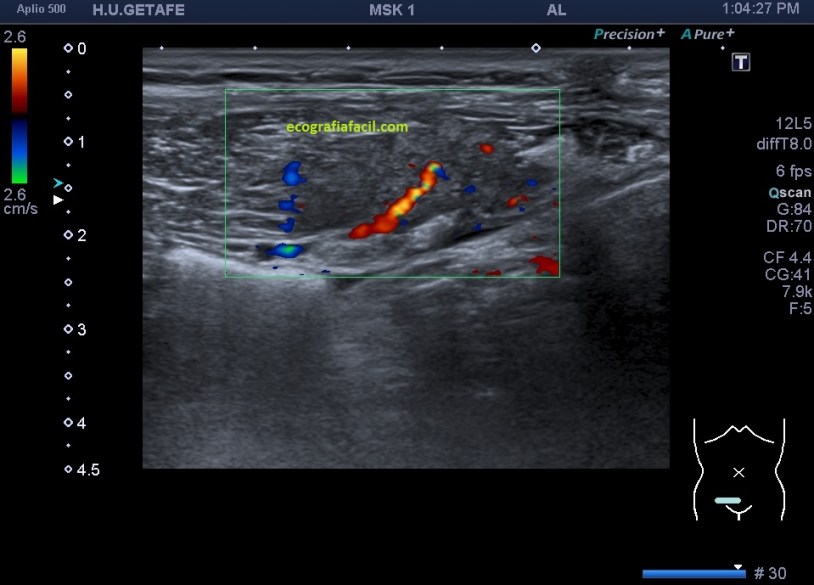

El estudio doppler arroja el hallazgo de un vaso importante que está alcanzando y nutriendo la región afectada. Puedes observar como es un vaso de alto flujo y de buen tamaño. No pude demostrar vascularización perimetral de la lesión.

Estos hallazgos dado el contexto clínico sugieren foco de endometriosis. En este caso eran focos o implantes de endometriosis que tras la cirugía pudieron quedar diseminados por el tejido muscular.